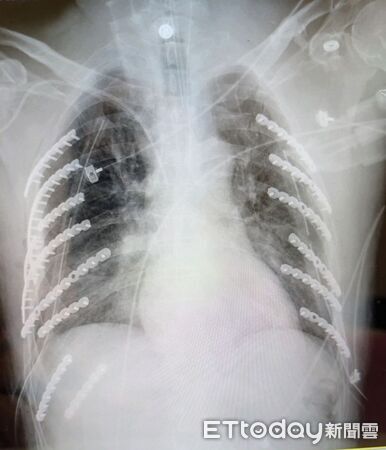

▲台中醫院胸腔外科團隊成功為患者進行鈦合金肋骨固定手術,三週後康復出院。(圖/記者游瓊華翻攝)

衛生福利部台中醫院胸腔外科何蕙如師指出,患者入院時胸腔X光片顯示雙側肋骨共二十八根中,有十四根斷裂,有的甚至斷成兩至三截,情況相當罕見。「比起一般肋骨骨折三至五根,他的傷勢幾乎是三倍以上」,同時還伴隨左鎖骨、脊柱裂傷及嚴重氣胸、呼吸衰竭。

醫療團隊經加護病房觀察後評估,雖斷裂數量多,但並未刺穿血管與肺葉,遂採兩階段手術方式,首階段植入八根、次階段再植入六根鈦合金鋼板,協助肋骨復位固定。術後患者恢復良好,三週後能自行行走出院。他笑說,「現在身上有十四根鋼骨,就像穿了金鐘罩一樣,連家人都說我成了鋼鐵人!」